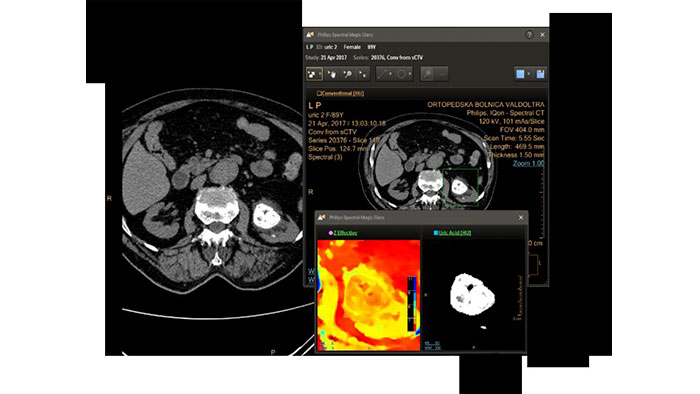

IQon Spectral CT Functionality

IQon Spectral CT is the only scanner to offer CT Spectral Light Magic Glass and CT Spectral Magic Glass on PACS, helping radiologists review and analyze multiple layers of spectral data at once, including on their PACS.

IQon Spectral CT* Functionality

The spectral viewer is optimized for analysis of spectral data sets from the IQon Spectral CT Scanner. Obtain a comprehensive overview of each patient quickly and easily, quantify quickly, and assist in diagnosis. It is designed to accommodate general spectral viewing needs with additional tools to assist in CT images analysis.